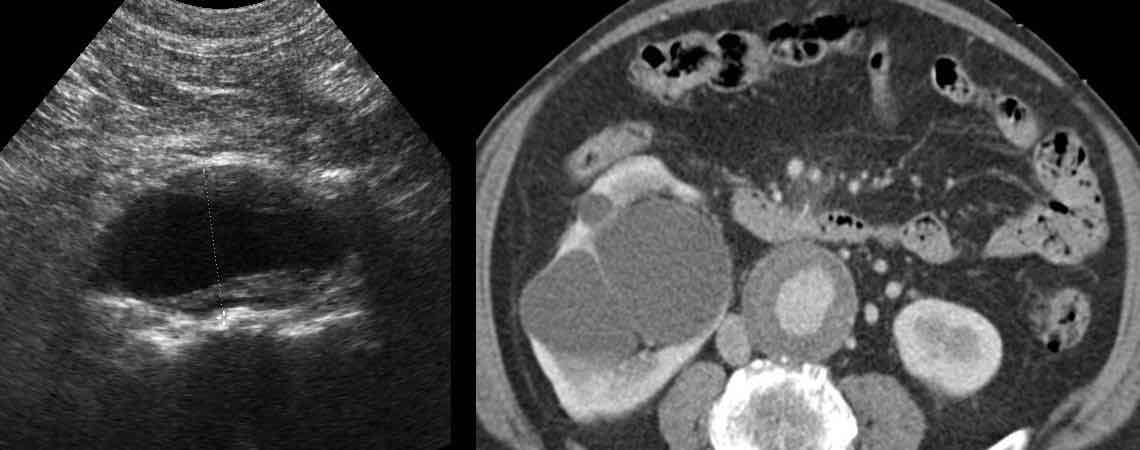

Bệnh nhân nam 85 tuổi này nhập viện với đau khu trú dữ dội, viêm phúc mạc khu trú và CRP 200, lâm sàng nghi ngờ viêm ruột thừa.

Siêu âm cho thấy một vùng nhỏ khu trú gồm mỡ tăng âm bị viêm (đầu mũi tên), chứa một ít dịch (*) và một phản âm khó lý giải (mũi tên trắng).

Chẩn đoán siêu âm dự kiến là viêm phần phụ mạc nối với vùng xuất huyết trung tâm nhỏ.

CT xác nhận thâm nhiễm mỡ khu trú và phát hiện thêm một bóng khí cũng như dày thành nhẹ của một quai ruột non lân cận.

Áp dụng từ gợi nhớ PSI-ABCD, tất cả các nguyên nhân đều được loại trừ, ngoại trừ dị vật sắc nhọn.

Sau khi tìm kiếm có chủ đích, một xương cá được phát hiện tại manh tràng (mũi tên xanh lá trên CT).

Rõ ràng, xương cá này đã gây ra thủng, và sau đó được đẩy đi bởi nội dung ruột non. Bệnh nhân được điều trị bằng kháng sinh đơn thuần và hồi phục hoàn toàn.